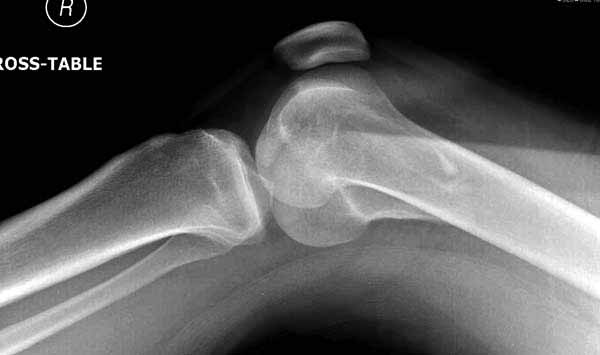

Однако в случае, представленном Константином Никитиным, не может быть применён ни ретроградный ни антеградный остеосинтез. Причина - нереально выполнить вышеуказанные необходимые требования, касающиеся дистальных блокирующих винтов. Из-за низкого перелома латерального мыщелка (перелом Hoffa) невозможно через него провести хотя бы 2 блокирующих винта, поскольку линия перелома мыщелка расположена либо на уровне верхушки межмыщелковой ямки либо незначительно проксимальнее. Поэтому авторам, с моей точки зрения, необходимо прислушаться к рекомендациям Джолдаса.

Рационально ориентироваться на качественный аспект - проблема или решается, или нет. Переломы типа 33C1 или C2 (то есть без фронтального раскалывания мыщелков, как на показанной Вами томограмме) при обычном качестве кости успешно можно фиксировать гвоздями с фронтальными винтами. Получается, их прочностных характеристик уже достаточно.